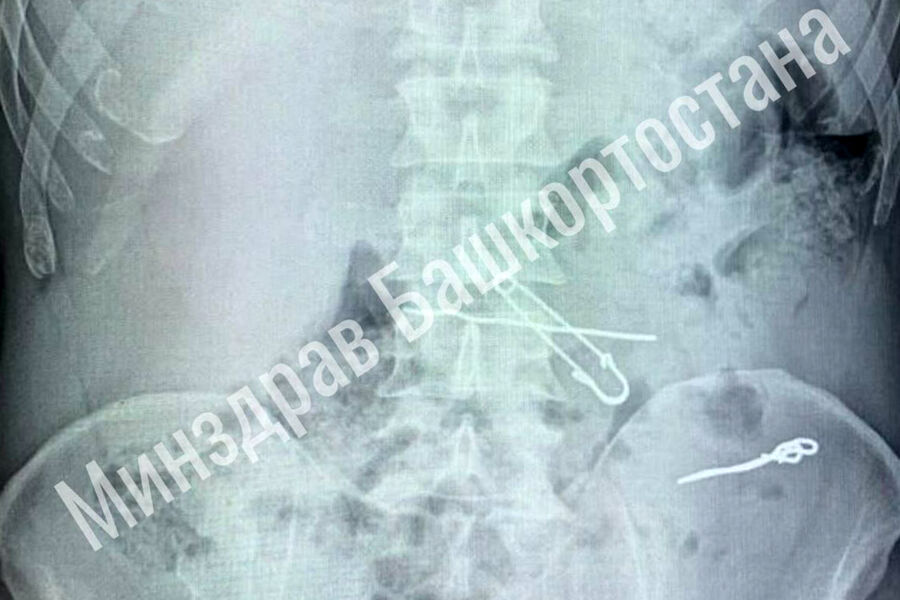

В больницу скорой медицинской помощи поступил мужчина с жалобами на сильные боли в животе. По результатам обследования выяснилось, что у него в толстой кишке находились три металлические скрепки длиной 47, 62 и 90 миллиметров, а в желудке — булавка и проволока.

Пациента срочно госпитализировали в отделение гнойной хирургии, где врачи успешно провели операцию по извлечению всех предметов. Во время вмешательства медики делали контрольные рентгеновские снимки, чтобы убедиться в полном удалении инородных тел. После операции мужчина успешно восстановился и был выписан из медицинского учреждения.